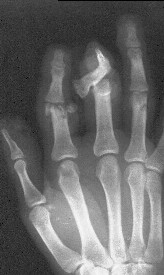

часть пальца висит на кожном лоскуте с латеральной стороны пальца шириной 1 см, повреждены сухожилия сгибателей и разгибателей), многооскольчатым переломом головки основной фаланги 2 пальца, рваной раной в проекции сустава, превышающей половину диаметра пальца (сухожилия целы)(снимок 1, снимок 2). Выполнена ПХО ран, МОС спицами трансартикулярно (снимок 3, снимок 4). При обсуждении тактики лечения возникли разногласия между врачом, выполнявшим ПХО, и заведующим. Зав. отделением считает, что выбранная тактика неверна, и необходимо было после проведения ПХО сделать вытяжение типа Черкес-Заде за пальцы. Просим высказать присутствующих свое мнение о выполненной операции и о дальнейшей тактике лечение больного. Заранее спасибо.

По моему мнению, избранный способ фиксации является правильным.